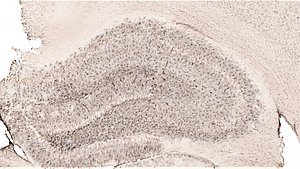

A - Nissl ķermenīši (neironu graudainais endoplazmatiskais tīkls) iekrāsoti ar krezilviolēto krāsvielu. B - žurkas hipokampa rajons (viens no galveniem rajoniem, kas piedalās atmiņas procesu realizācijā), kurā iekrāsots proteīns sinaptofizīns (atbild par sinaptisko plasticitāti un atmiņas procesiem). Bildes: V. Piļipenko.